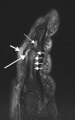

thumb|[[Magnetic resonance imaging|Magnetic resonance images of the fingers in psoriatic arthritis. Shown are T1-weighted (a) pre-contrast and (b) post-contrast coronal images. Enhancement of the synovial membrane at the third and fourth proximal interphalangeal (PIP) and distal interphalangeal (DIP) joints is seen, indicating active synovitis (inflammation of the synovial membrane; large arrows). There is joint space narrowing with bone proliferation at the third PIP joint and erosions are present at the fourth DIP joint (white circle). Extracapsular enhancement (small arrows) is seen medial to the third and fourth PIP joints, indicating probable enthesitis (inflammation of a tendon insertion).]] thumb|[[Sagittal plane|Sagittal magnetic resonance images of the ankle region in psoriatic arthritis. (a) Short tau inversion recovery (STIR) image, showing high signal intensity at the Achilles tendon insertion (enthesitis, thick arrow) and in the synovium of the ankle joint (synovitis, long thin arrow). Bone marrow edema is seen at the tendon insertion (short thin arrow). (b, c) T1 weighted images of a different section of the same patient, before (panel b) and after (panel c) intravenous contrast injection, confirm inflammation (large arrow) at the enthesis and reveal bone erosion at tendon insertion (short thin arrows).]] There is no definitive test to diagnose psoriatic arthritis. Symptoms of psoriatic arthritis may closely resemble other diseases, including rheumatoid arthritis. A rheumatologist (a physician specializing in autoimmune diseases) may use physical examinations, health history, blood tests and x-rays to accurately diagnose psoriatic arthritis.

Magnetic resonance image of the index finger in psoriatic arthritis (mutilans form). Shown is a T2 weighted fat suppressed sagittal image. Focal increased signal (probable erosion) is seen at the base of the middle phalanx (long thin arrow). There is synovitis at the proximal interphalangeal joint (long thick arrow) plus increased signal in the overlying soft tissues indicating edema (short thick arrow). There is also diffuse bone edema (short thin arrows) involving the head of the proximal phalanx and extending distally down the shaft.